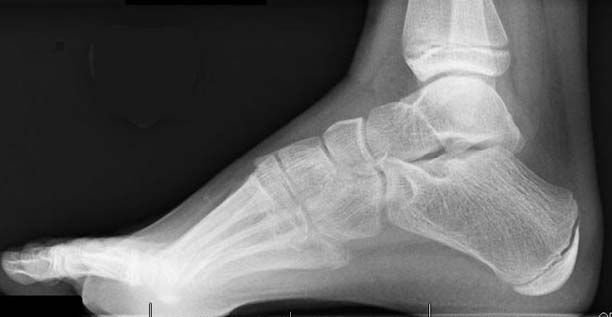

Atrophy associated with mild-to-moderate sensory loss. Charcot-Marie-Tooth disease CMT is one of a group of disorders that cause damage to the peripheral nervesthe nerves that transmit information and signals from the brain and spinal cord to and from the rest of the body as well as sensory information such as touch back to the spinal cord and brain. Pes cavus and hammer toe deformities with twisting of the ankle.

Severe atrophy of all intrinsic short foot muscles which have been replaced by fat tissue. Taken together results from these articles support the concept that genetic causes of Charcot-Marie-Tooth disease serve as a living microarray system to identify molecules necessary for normal peripheral nervous system function. There is linear thickening of several cauda equina equina extending from the leve.

Gallardo E Garcia A Combarros O Berciano J. Severe atrophy of all intrinsic short foot muscles which have been replaced by fat tissue. CharcotMarieTooth disease CMTD also known as hereditary motor and sensory neuropathy HMSN is the most frequent form of inherited polyneuropathy with a prevalence ratio of 17-40 cases per 100 000 inhabitants. Charcot-Marie-Tooth disease is a hereditary hypertrophic neuropathy. Pes cavus and hammer toe deformities with twisting of the ankle. MR and CT imaging has become more common in the evaluation of CMT to identify areas of disease involvement. What is Charcot-Marie-Tooth disease. Its also known as hereditary motor and sensory neuropathy HMSN or peroneal muscular atrophy PMA. Distal muscle weakness.